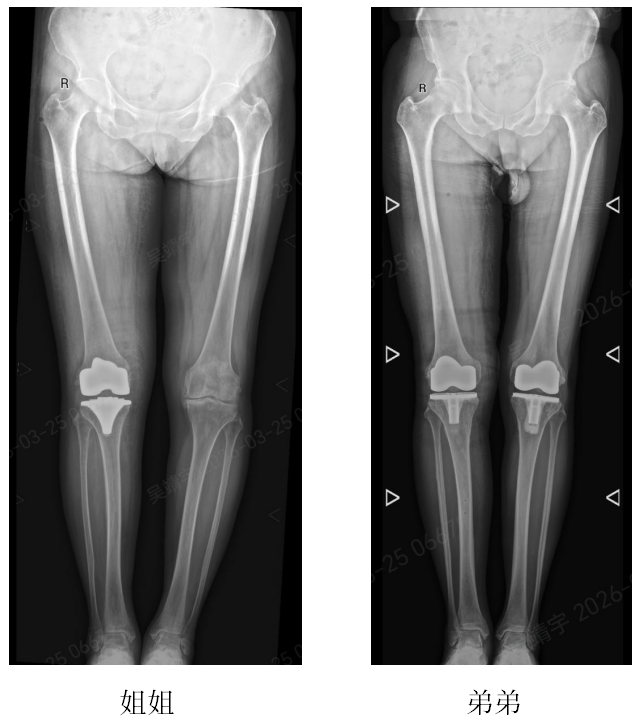

近日,北京积水潭医院郑州医院(郑州市中心医院)关节外科主任杨锴、副主任医师吴靖宇采用骨科手术机器人辅助全膝关节置换术,成功为 72 岁的姐姐沙女士与 64 岁的弟弟沙先生实施右侧人工全膝关节置换手术。术后,姐弟二人膝关节功能恢复良好。

姐弟二人多年来均被严重的膝关节骨性关节炎困扰,膝关节疼痛、肿胀、活动受限,日常行走、上下楼梯都十分困难,严重影响生活质量。随着年龄增长,病情愈发严重,保守治疗早已无法缓解症状,都希望可以使用手术改善生活质量。

入院后,杨锴主任立即为姐弟二人进行全面细致的检查,精准评估膝关节病变程度、骨骼形态及身体基础状况。针对两位患者的病情,结合机器人手术的技术优势,团队制定了个性化的手术方案。